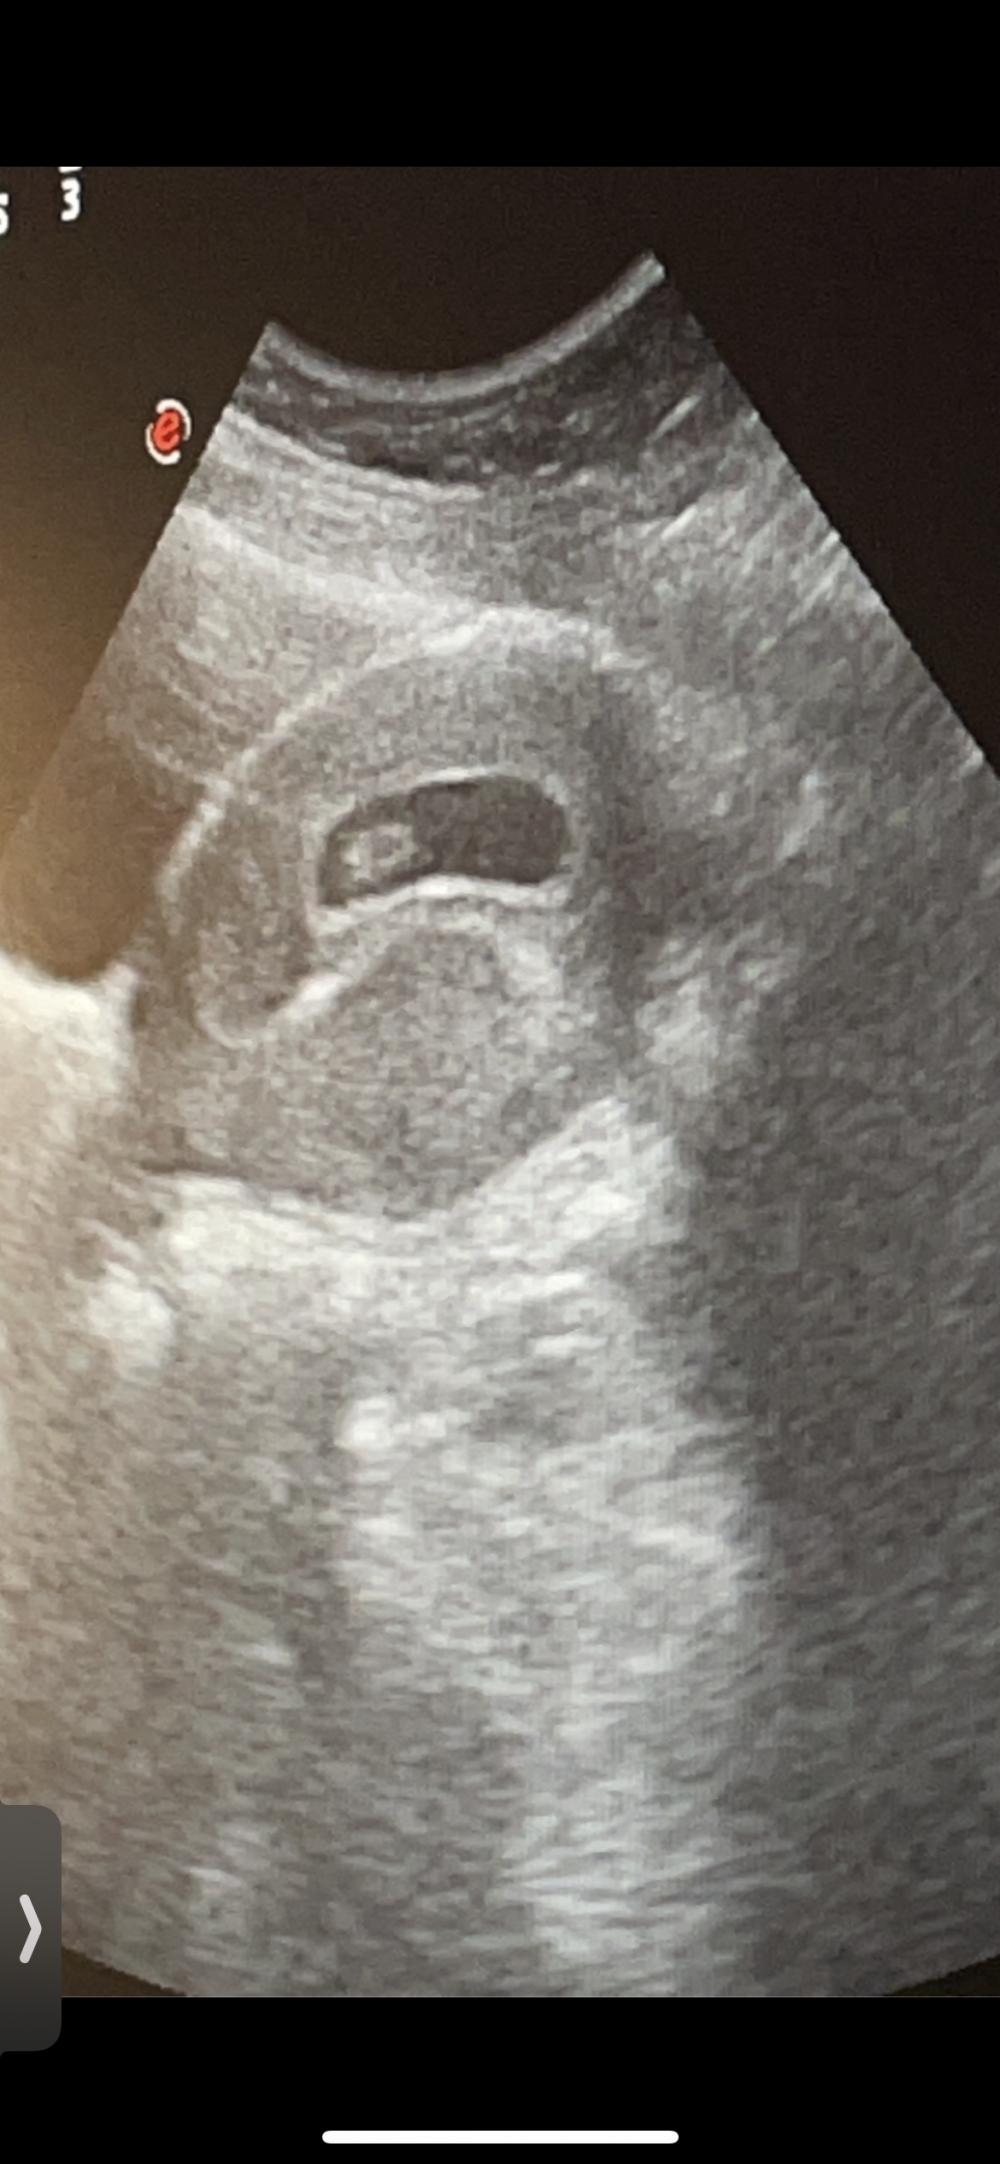

يلا انا بشوف هذا سوناري بالثامن

هذا هو بالاسبوع الثامن